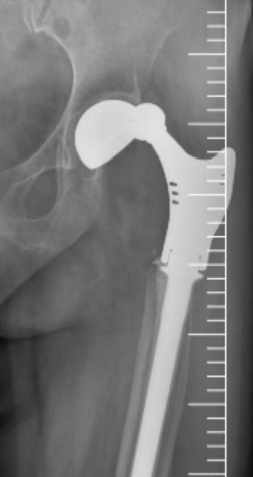

接诊后,成人ai 骨病与骨肿瘤科主任秦光华团队展开全面评估,影像学检查显示多重棘手问题:

人工髋关节脱位明确且假体松动明显,

患侧脱位后解剖结构紊乱,进一步增加治疗难度。

术前X线影像检查